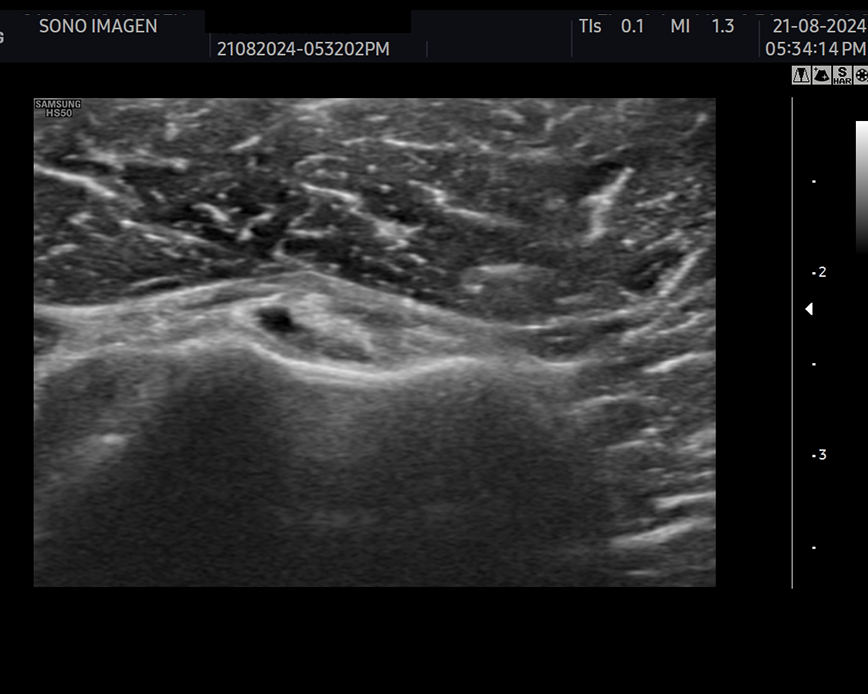

Ecografía de rodilla

- evaluación del dolor de rodilla

- lesiones de tejidos blandos: tendinosis, desgarros ligamentosos, rupturas meniscales.

- derrame articular

- inflamación o infección

- evaluación de lesiones deportivas

- quiste de Baker

- seguimiento postoperatorio

- traumatismos